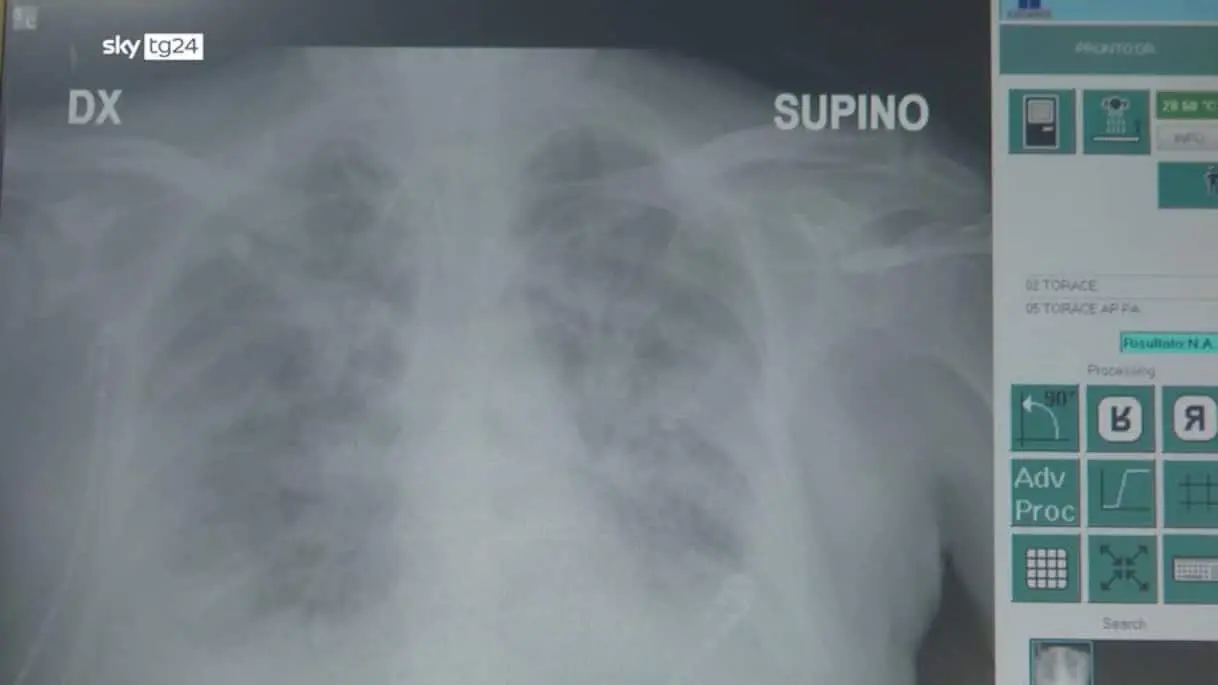

Polmonite interstiziale, soggetti fragili più a rischio vita

Polmonite interstiziale, di cosa si tratta e chi è a rischio